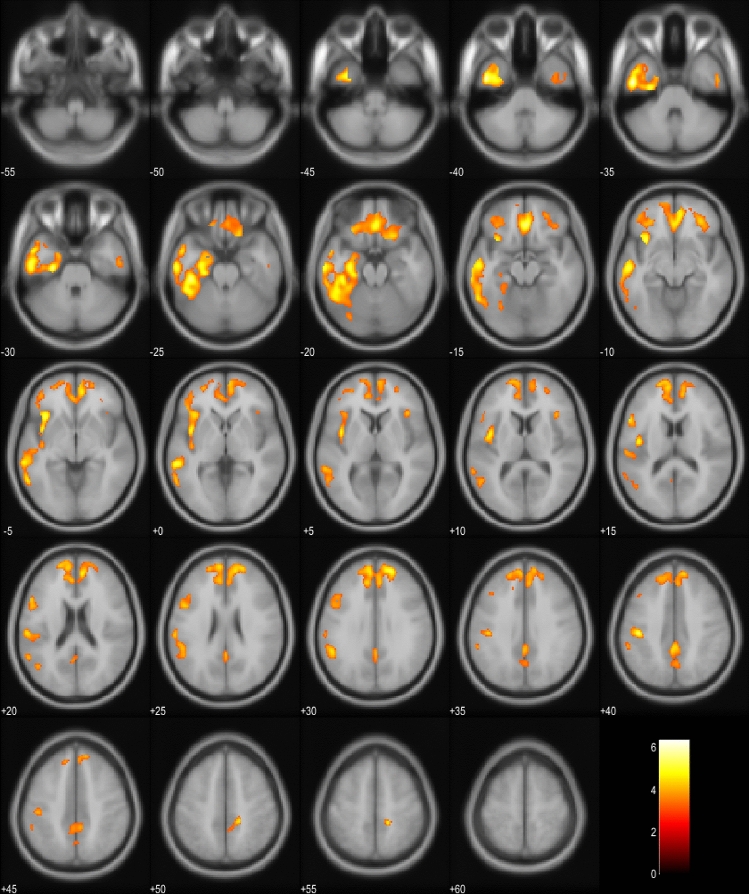

18FDG-PET scans of the EP + patients were compared to the scans of the EP- patients in the whole cohort and also in the subgroup including only bvFTD patients (Fig. 1a, b). In the whole cohort, EP + patients showed significant hypometabolism predominantly in the left hemisphere in the temporal and medial frontal lobes. In the bvFTD subgroup, similar results were obtained in the EP + patients with hypometabolism detected mostly in the left temporal lobe. Also, the SCP and the frontal lobes showed hypometabolism. Comparison between EP + bvFTD patients and patients with PSP or CBD indicated that the bvFTD patients specifically showed hypometabolism in cerebellar lingula and SCP (Fig. 1c). No differences were observed in the cortical regions.